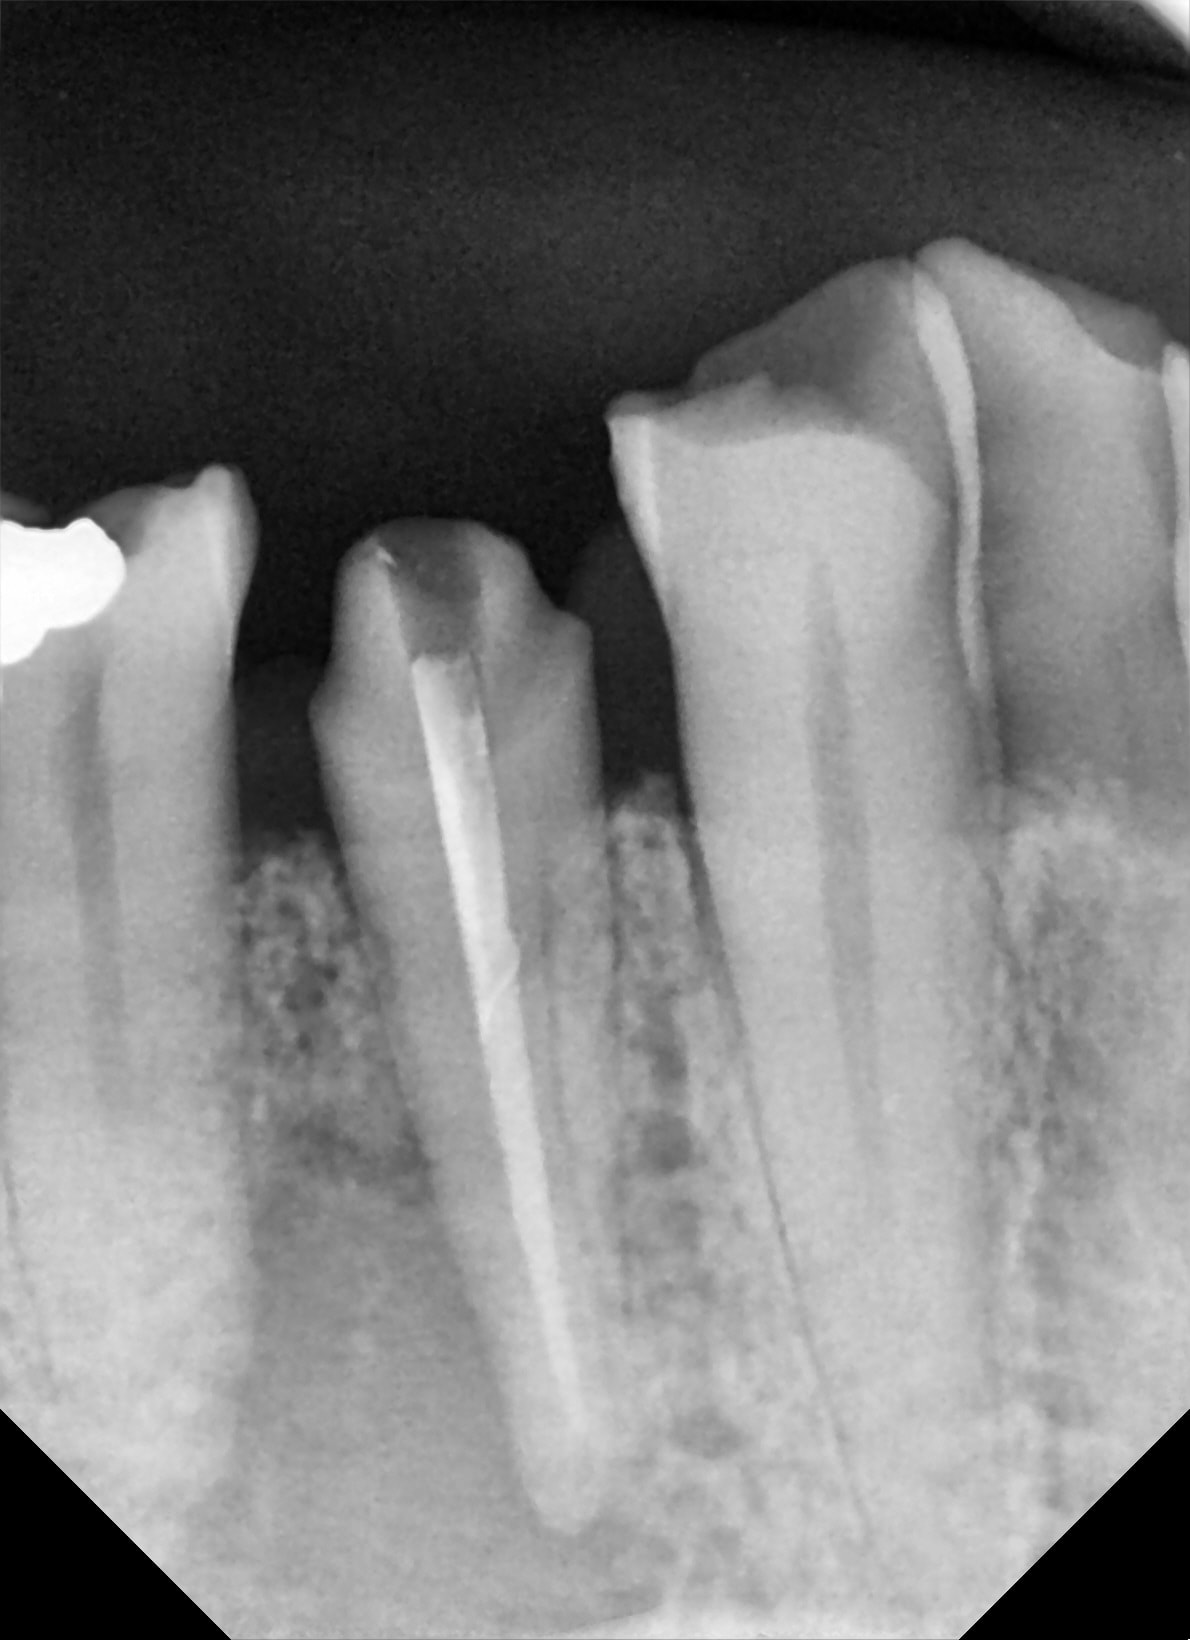

37

apres une endo de sauvage ,bien bourrée au compactor , 1 petit aller retour pour cette 37 .

pratique pour detartrer la face distale :-))

je vous tiens au courant .